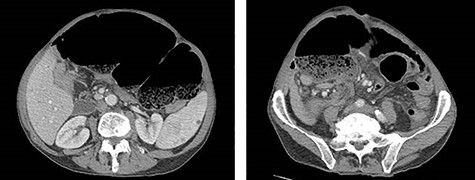

Eleven months after PD, the patient presented to the emergency department with abdominal pain, distension and obstipation. He was hemodynamically stable, with physical examination notable for large incisional hernia with severe abdominal distension and tenderness without peritonitis. Computed tomography scan of the abdomen demonstrated a coffee-bean shaped cecum in the left upper quadrant with dilated colon and evidence of mesenteric swirling in the right lower quadrant, consistent with cecal volvulus (Fig. 2). The patient was taken to the operating room for urgent exploration.

CT of the abdomen and pelvis demonstrating coffee-bean shaped cecum in left upper quadrant dilated to 12 cm, consistent with cecal volvulus.